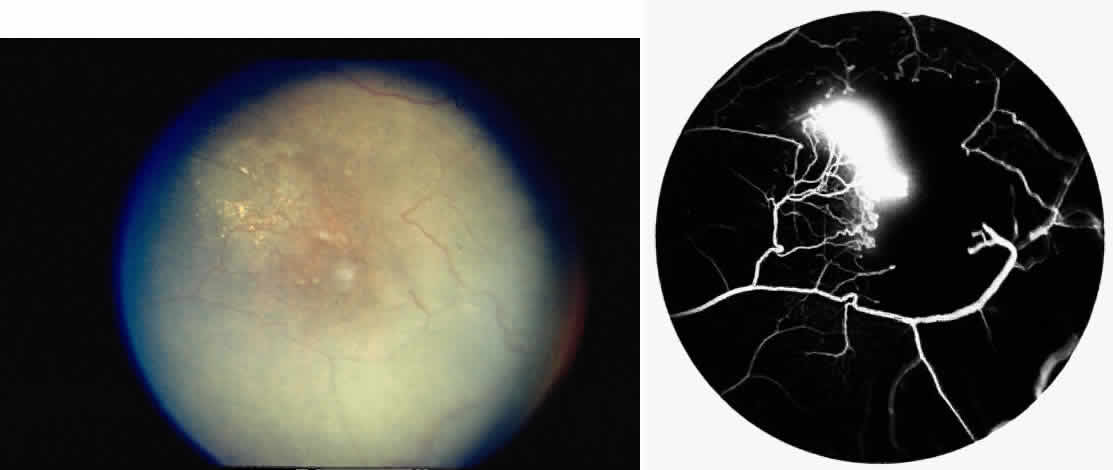

Choroidal Vascular Occlusions

Choroidal vascular occlusions may occur focally at the level of the choroidal precapillary arteriole or capillary bed (Elschnig's spots) or from posterior ciliary artery occlusion. Although focal precapillary arteriole occlusions have not been specifically identified with sickle cell disease, clinical and histopathologic evidence of spontaneous posterior ciliary artery occlusions have been reported in sickle cell disease.109,110 The findings are similar to those described following compression of the eye during general anesthesia and after heavy peripheral photocoagulation.111,112 In the acute phase, the occlusions appear as white, circumscribed, triangular patches at the level of the retinal pigment epithelium and outer retina. Over the following weeks, the white lesions fade and retinal pigment epithelial mottling develops (Fig. 15). Since patients with acute ciliary artery occlusions may be asymptomatic and the diagnosis is often based solely on the appearance of peripheral pigment mottling, the frequency of this complication remains uncertain.

Fig. 15. A 25-year-old man with homozygous sickle cell anemia and proliferative sickle retinopathy. A. Photograph demonstrating nonperfusion and wedge-shaped pigment mottling representing a choroidal infarction. B. Fluorescein angiogram demonstrating hyperfluorescence at the level of the retinal pigment epithelium.